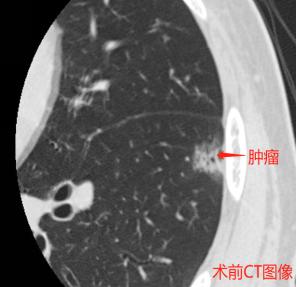

患者李某,男性,66岁,因“查体发现左肺下叶结节5月”入院,患者既往有长期吸烟史,入院后完善相关检查,患者患有窦性心动过缓。程思强主任组织胸外科全体医生经过充分的论证,仔细阅片,通过三维成像为该患者制定详细的手术方案,慎重考虑手术的每个环节,决定独立完成“全胸腔镜下解剖性肺段切除+淋巴结清扫术”。

术前图像